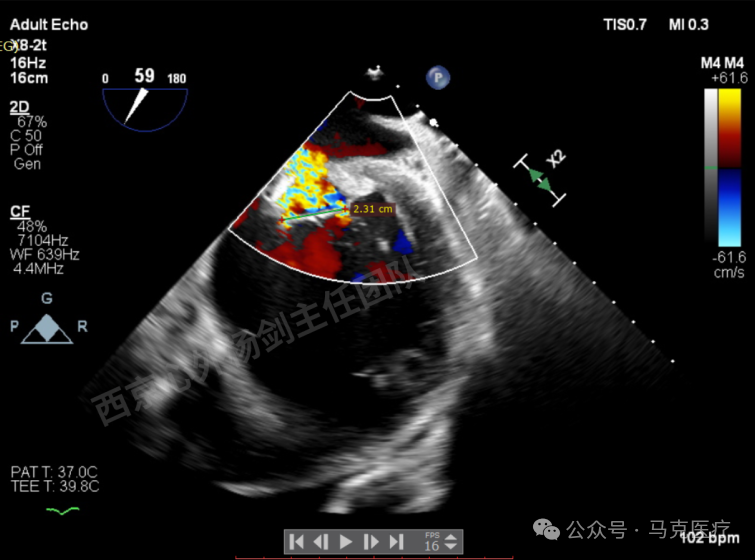

二尖瓣后叶栓系严重,前叶相对错位,反流束沿2区分布广泛,2偏3区处存在反流。

反流宽度至少23mm,因影像调整困难,考虑实际反流更宽。